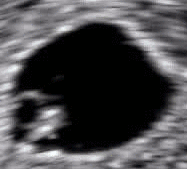

A gestational sac can be reliably seen on transvaginal ultrasound by 5 weeks' gestational age (approximately 3 weeks after ovulation). The embryo should be seen by the time the gestational sac measures 25 mm, about five-and-a-half weeks.[10] The heartbeat is usually seen on transvaginal ultrasound by the time the embryo measures 5 mm, but may not be visible until the embryo reaches 19 mm, around 7 weeks' gestational age.[5][11][12] Coincidentally, most miscarriages also happen by 7 weeks' gestation. The rate of miscarriage, especially threatened miscarriage, drops significantly after normal heartbeat is detected, and after 13 weeks.[13]

Embryo at 5 weeks and 1 day of gestational age (at top left) with discernible heartbeat

Embryo at 5 weeks and 5 days of gestational age with discernible heartbeat